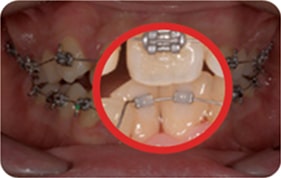

Case 3

2017. 10. 11

2017. 12. 26

2018. 02. 26